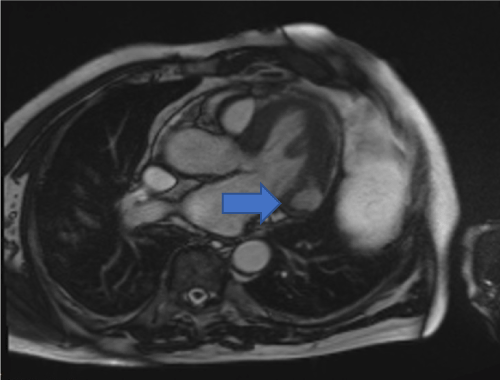

Cardiac MRI showed mildly increased left ventricular (LV) volume indices (End Diastolic Volume - 148mls, End Diastolic Volume Indexed - 71mls, and End Systolic Volume - 75mls, End Systolic Volume Indexed - 31mls) and mildly impaired LV systolic function with LV ejection fraction 48%, normal right ventricular systolic function, and a well circumscribed lesion in the basal lateral wall (Figures 3 and 4). The lesion was hypointense in TruFISP, hyperintense in T1 and T2 weighted images which suggested the lesion did not contain water or fat.  The lesion showed strong homogenous high intake enhancement with gadolinium contrast both in the early and late phase suggesting it was highly vascular. The perfusion study demonstrated a fixed perfusion defect around the lesion. In the gadolinium study, there was no evidence of LV or RV thrombus in the early phase while in the late phase, there was a patch of full thickness late gadolinium enhancement (LGE) around the lesion (Figure 5).

A CMR 6 months later shows resolution of the lesion but persisting LGE in the left circumflex territory (Figures 4 and 5).

Figure 4. Hypointense lesion seen in basal lateral wall of left ventricle in cross cut long axis view SSFP cine (Blue arrow).

Given the transience of the left ventricular abnormality and its location, it was concluded that the culprit coronary lesion in the first instance was likely to have been the left circumflex: the CMR abnormalities represent a left ventricular aneurysm and a pericardial effusion related to post cardiac injury (Dressler’s) syndrome (Figures 6 and 7).

Figures 6: Still images from 6 monthly follow up scan from SSFP cine sequences showing resolution of left ventricular aneurysm